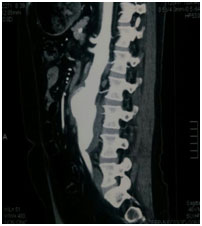

6th Oct 2017: It gives us pride & pleasure to announce that, the first ever procedure EVAR (endovascular aortic repair) has been done in Dr. Ziauddin Hospital (Clifton campus), under the team members;

Dr. Kamal Yusuf, Dr. Muhammad Ali and Dr. Ameer from Jordan played the key role in managing the whole process.